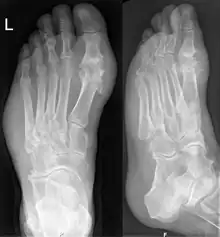

Les radiographies sont normales au début et ne servent qu'à exclure un autre diagnostic. En revanche elles servent à rechercher les conséquences osseuses ou articulaires de la goutte chronique (arthropathie goutteuse).